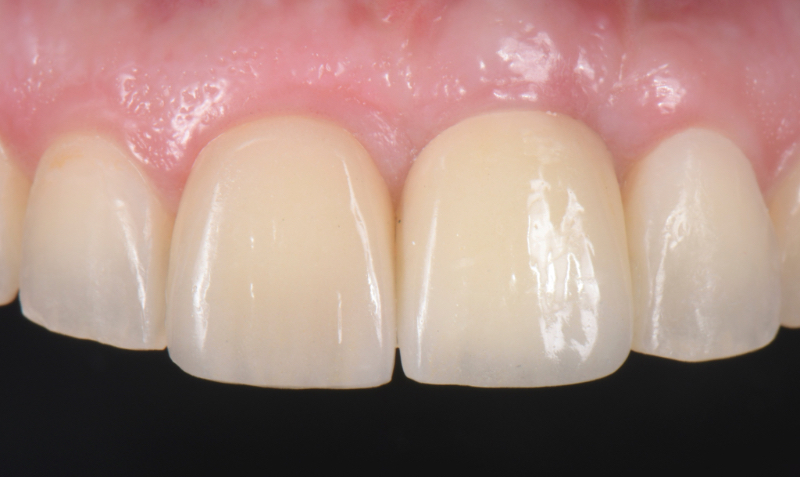

The esthetic success of an anterior implant-supported restoration mostly depends on having a soft-tissue architecture indistinguishable from the adjacent teeth. One of the most critical steps to achieve this “esthetic success” is correctly using the provisional restoration to optimize and properly contour (groom) the peri-implant tissue anatomy.

Once the optimal emergence profile has been developed, we need to communicate and transfer this information properly to the laboratory. Unfortunately, all implant companies provide stock round impression copings that do not precisely transfer the soft-tissue contours. A simple protocol to communicate this information is described here.

This visual essay walks through a step-by-step description of how to fabricate a personalized impression coping with transfer ofthe peri-implant tissue anatomy properly.